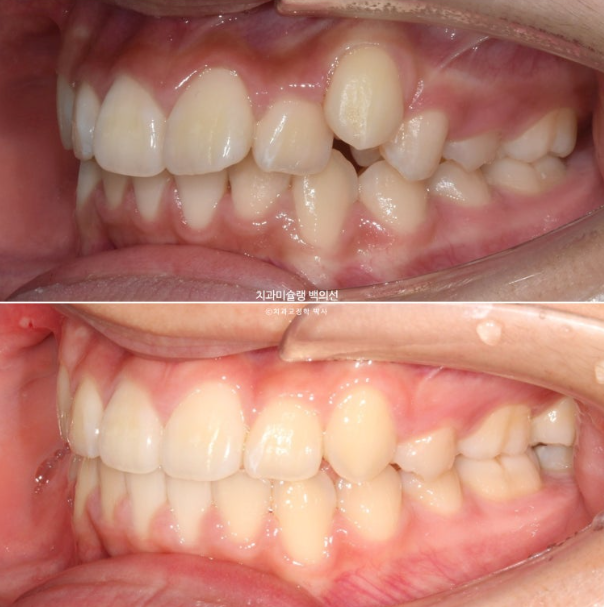

치료시작 1년째 모습입니다.

24.02

상악 발치공간은 편측으로 약 1/3 남아있으며 아직 한쪽 제2대구치가 나오지 않은 상황입니다.

두번째 큰어금니가 나오길 기다리며 치료를 천천히 이어갑니다.

치료시작 2년 3개월차, 드디어 치료를 마무리 합니다.

25.05

중심선은 잘 맞으며 교합은 깔끔합니다.

위에만 작은어금니를 발치하면 교합이 괜찮나요?

하는 질문을 많이 하십니다.

상악만 발치교정 결과 교합은 이러합니다.

23.02~25.05

뻗치치도 옥니처럼 뒤로 너무 들어가지도 않은 적절한 앞니 각도

입술 돌출 역시 과하지 않게 입술 볼륨감을 유지한채 적당히 들어갔습니다.

결과에서 보듯 작은어금니 4개 발치는 불필요했습니다.

윗니돌출이 해소가 되면서 입술이 편하게 다물립니다.

치료당시 아직 중학생이라 성장에 의해 아래턱이 조금 성장했습니다.